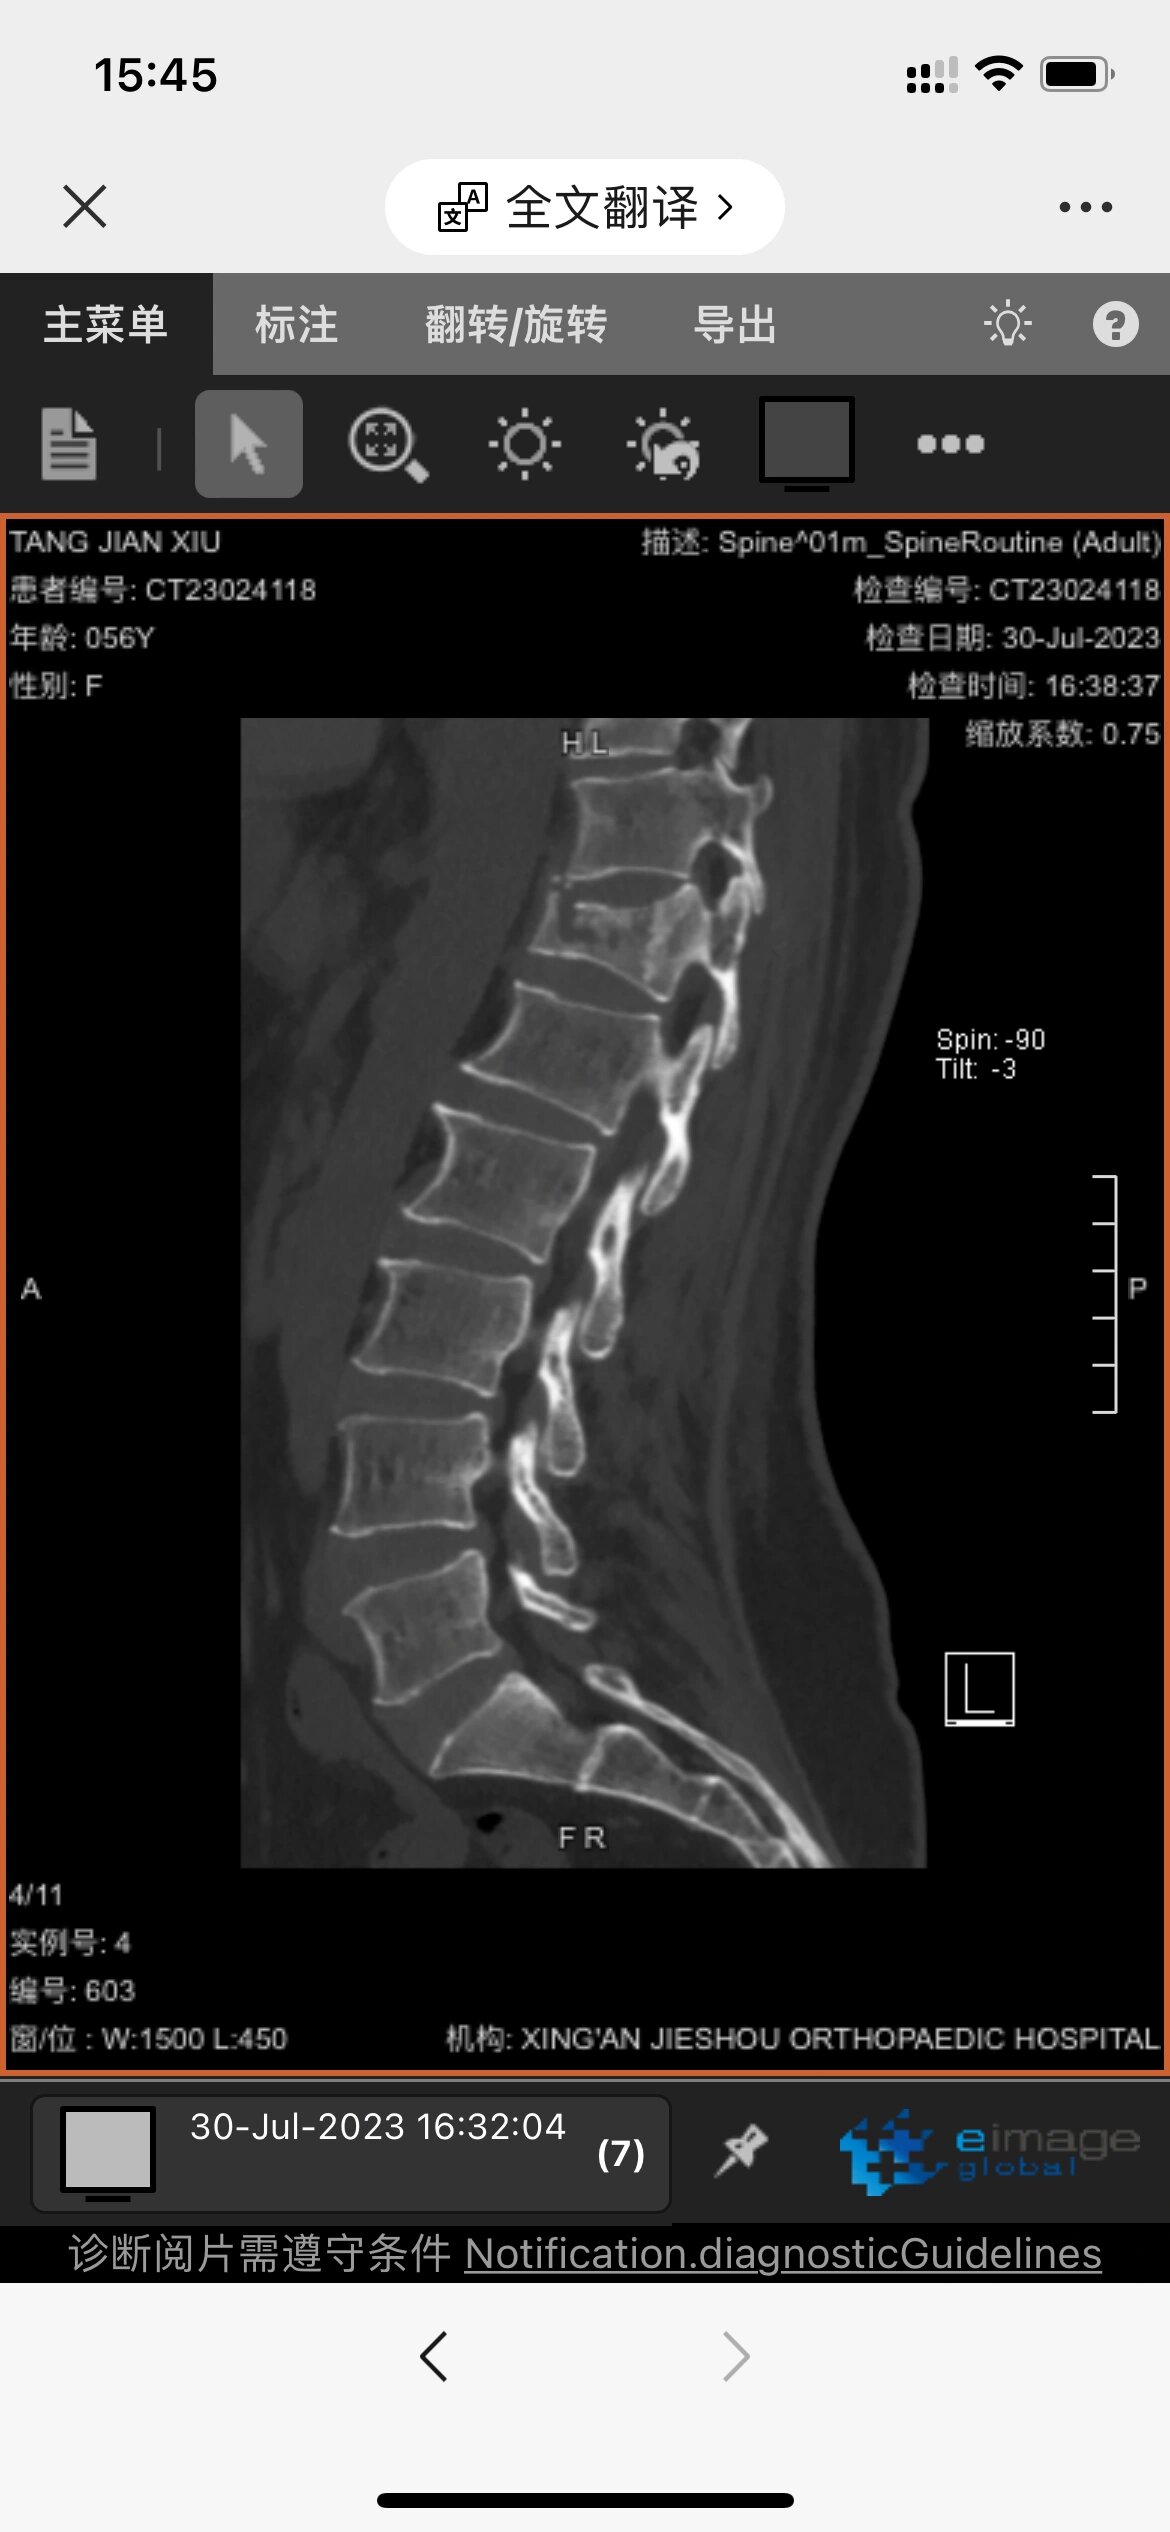

腰椎压缩性骨折保守治疗第56天心得分享

腰4椎体骨折pvp吓我一跳

腰4椎体骨折